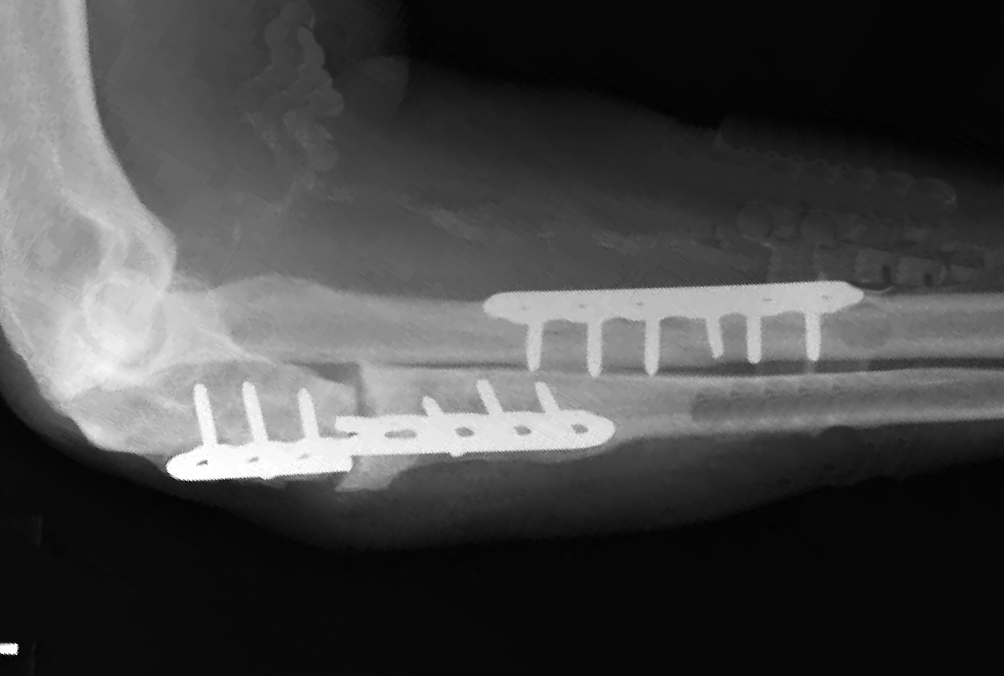

- Surgery is required in the majority of cases and first involves rigid fixation of the radius. This is followed by intraoperative assessment of DRUJ stability.

- Volar plate fixation

- Most common surgical approach

- Fixation may be more difficult when the fracture is in the distal third of the radius, where it may only be possible to insert two screws distal to the fracture line in these cases if using a 3.5-mm straight plate.1 Modern T-plates provide better fixation in the distal fragment by allowing additional screws in the distal fragment.

- Open reduction of the DRUJ11

- Sometimes necessary when the DRUJ cannot be reduced closed.

- The TFCC should be repaired and/or the forearm pinned in supination.

- Followed by immobilization with a splint or cast and the elbow in supination.